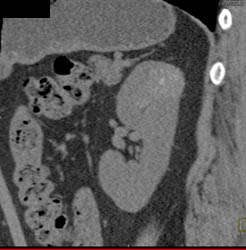

High Density Renal Cyst